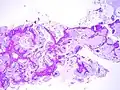

Mucinous BAC

Non-mucinous BAC